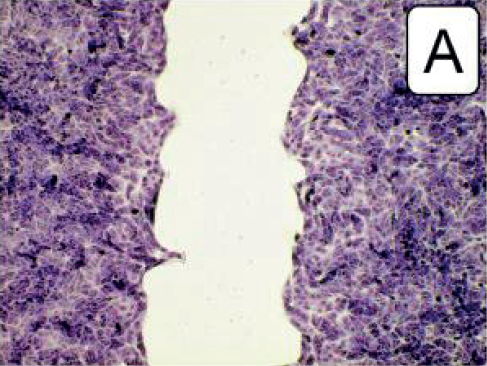

Untersuchung kultivierter Nierenzellen durch Prof. P. Dartsch** Ergebnis: schnellere Regeneration

**“Mikroskopische Darstellung der förderlichen Wirkung des Wasserstoffwassers von misterwater auf die Zellregeneration kultivierter Nierenzellen innerhalb von 12 Stunden. (A) Unbehandelte Kontrolle. (B) Reduzierter zellfreier Raum und damit bessere Zellregeneration durch Verwendung von 40 Vol% Wasserstoffwasser im Kulturmedium. (C) Größerer zellfreier Raum und damit schlechtere Zellregeneration durch Verwendung von 40 Vol% Stillem Wasser (= Ausgangswasser) im Kulturmedium. Fixierte und angefärbte Präparate im Olympus IX-50 Inversmikroskop mit 10x Planachromat und Olympus E-10 bei 4 Megapixeln Auflösung im Durchlicht-Hellfeld-Verfahren.“ (Prof. P. Dartsch, 20.06.2021: Förderliche Wirkeffekte des Wasserstoffwassers der misterwaterGmbH, Untersuchungen mit kultivierten Nierenzellen; verwendet wurde Wasserstoffwasser aus dem misterwater® Lourdes Generator)